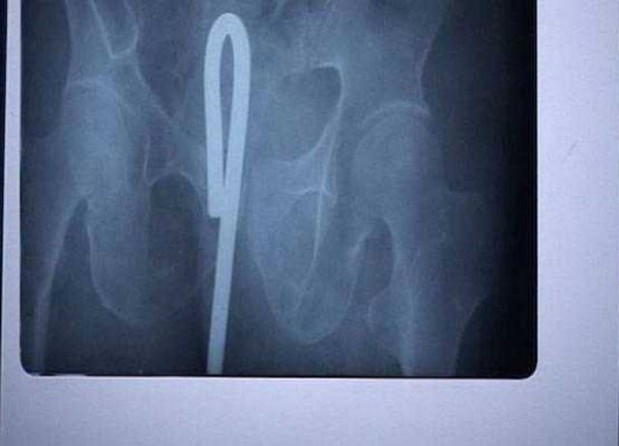

#21 Viinipullo miehen pyllyssä ja metallilanka, jolla hän yritti saada sitä pois